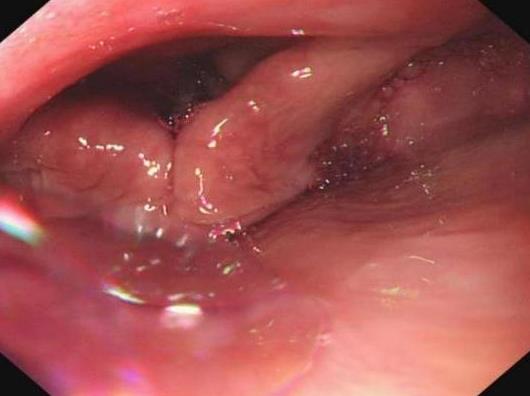

摘要:目的 探究经中鼻甲基板入路的手术技巧及临床效果,旨在系统评估一种兼具良好手术视野和微创性的蝶窦开放径路。方法 回顾性分析2019年9月-2023年9月该院收治的35例孤立性蝶窦病变或单侧蝶窦伴毗邻筛窦受累患者的临床资料,均经中鼻甲基板入路的“四步”程序化操作开放蝶窦。观察手术相关情况和并发症发生情况;采用视觉模拟评分法(VAS)评分,评估头痛和流涕等症状改善情况;采用改良隆德-肯尼迪(MLK)评分,评价术腔恢复状况。结果 所有患者术中保留钩突、中鼻甲和筛泡,26例(74.3%)保留上鼻甲;所有患者均达到临床治愈标准,表现为:术腔引流通畅,黏膜完全上皮化,以及蝶窦开口维持良好开放状态。术后病理显示:蝶窦霉菌病19例(54.3%),蝶窦息肉7例(20.0%),蝶窦黏膜慢性炎症9例(25.7%)。所有患者均未发生严重并发症,仅1例(2.9%)于术后12 d出现中鼻甲创面渗血,经电凝止血后治愈。头痛VAS评分由术前的(4.71±1.66)分,降至术后的(0.83±0.39)分,手术前后比较,差异有统计学意义(t = 13.71,P < 0.01);流涕VAS评分由术前的4.00(0.00,6.00)分,降至术后的0.00(0.00,1.00)分,手术前后比较,差异有统计学意义(Z = -4.47,P < 0.01);手术前后嗅觉减退VAS评分比较,差异无统计学意义(P > 0.05)。MLK评分由术前的4.50(2.00,4.00)分降至1.00(0.00,1.00)分,手术前后比较,差异有统计学意义(Z = -5.20,P < 0.01)。结论 经中鼻甲基板入路蝶窦开放术,严格遵循鼻窦解剖层次,在最大限度地保留鼻腔生理结构的前提下,可获得理想的术野暴露。该术式对于局限于蝶窦及后组筛窦的病变,具有确切的临床疗效。值得应用于临床。